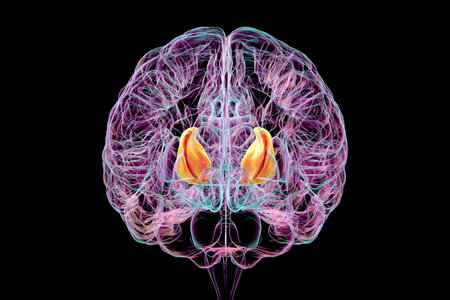

Human brain with highlighted internal capsule, crucial for transmitting motor and sensory signals, 3D illustration. Front view.